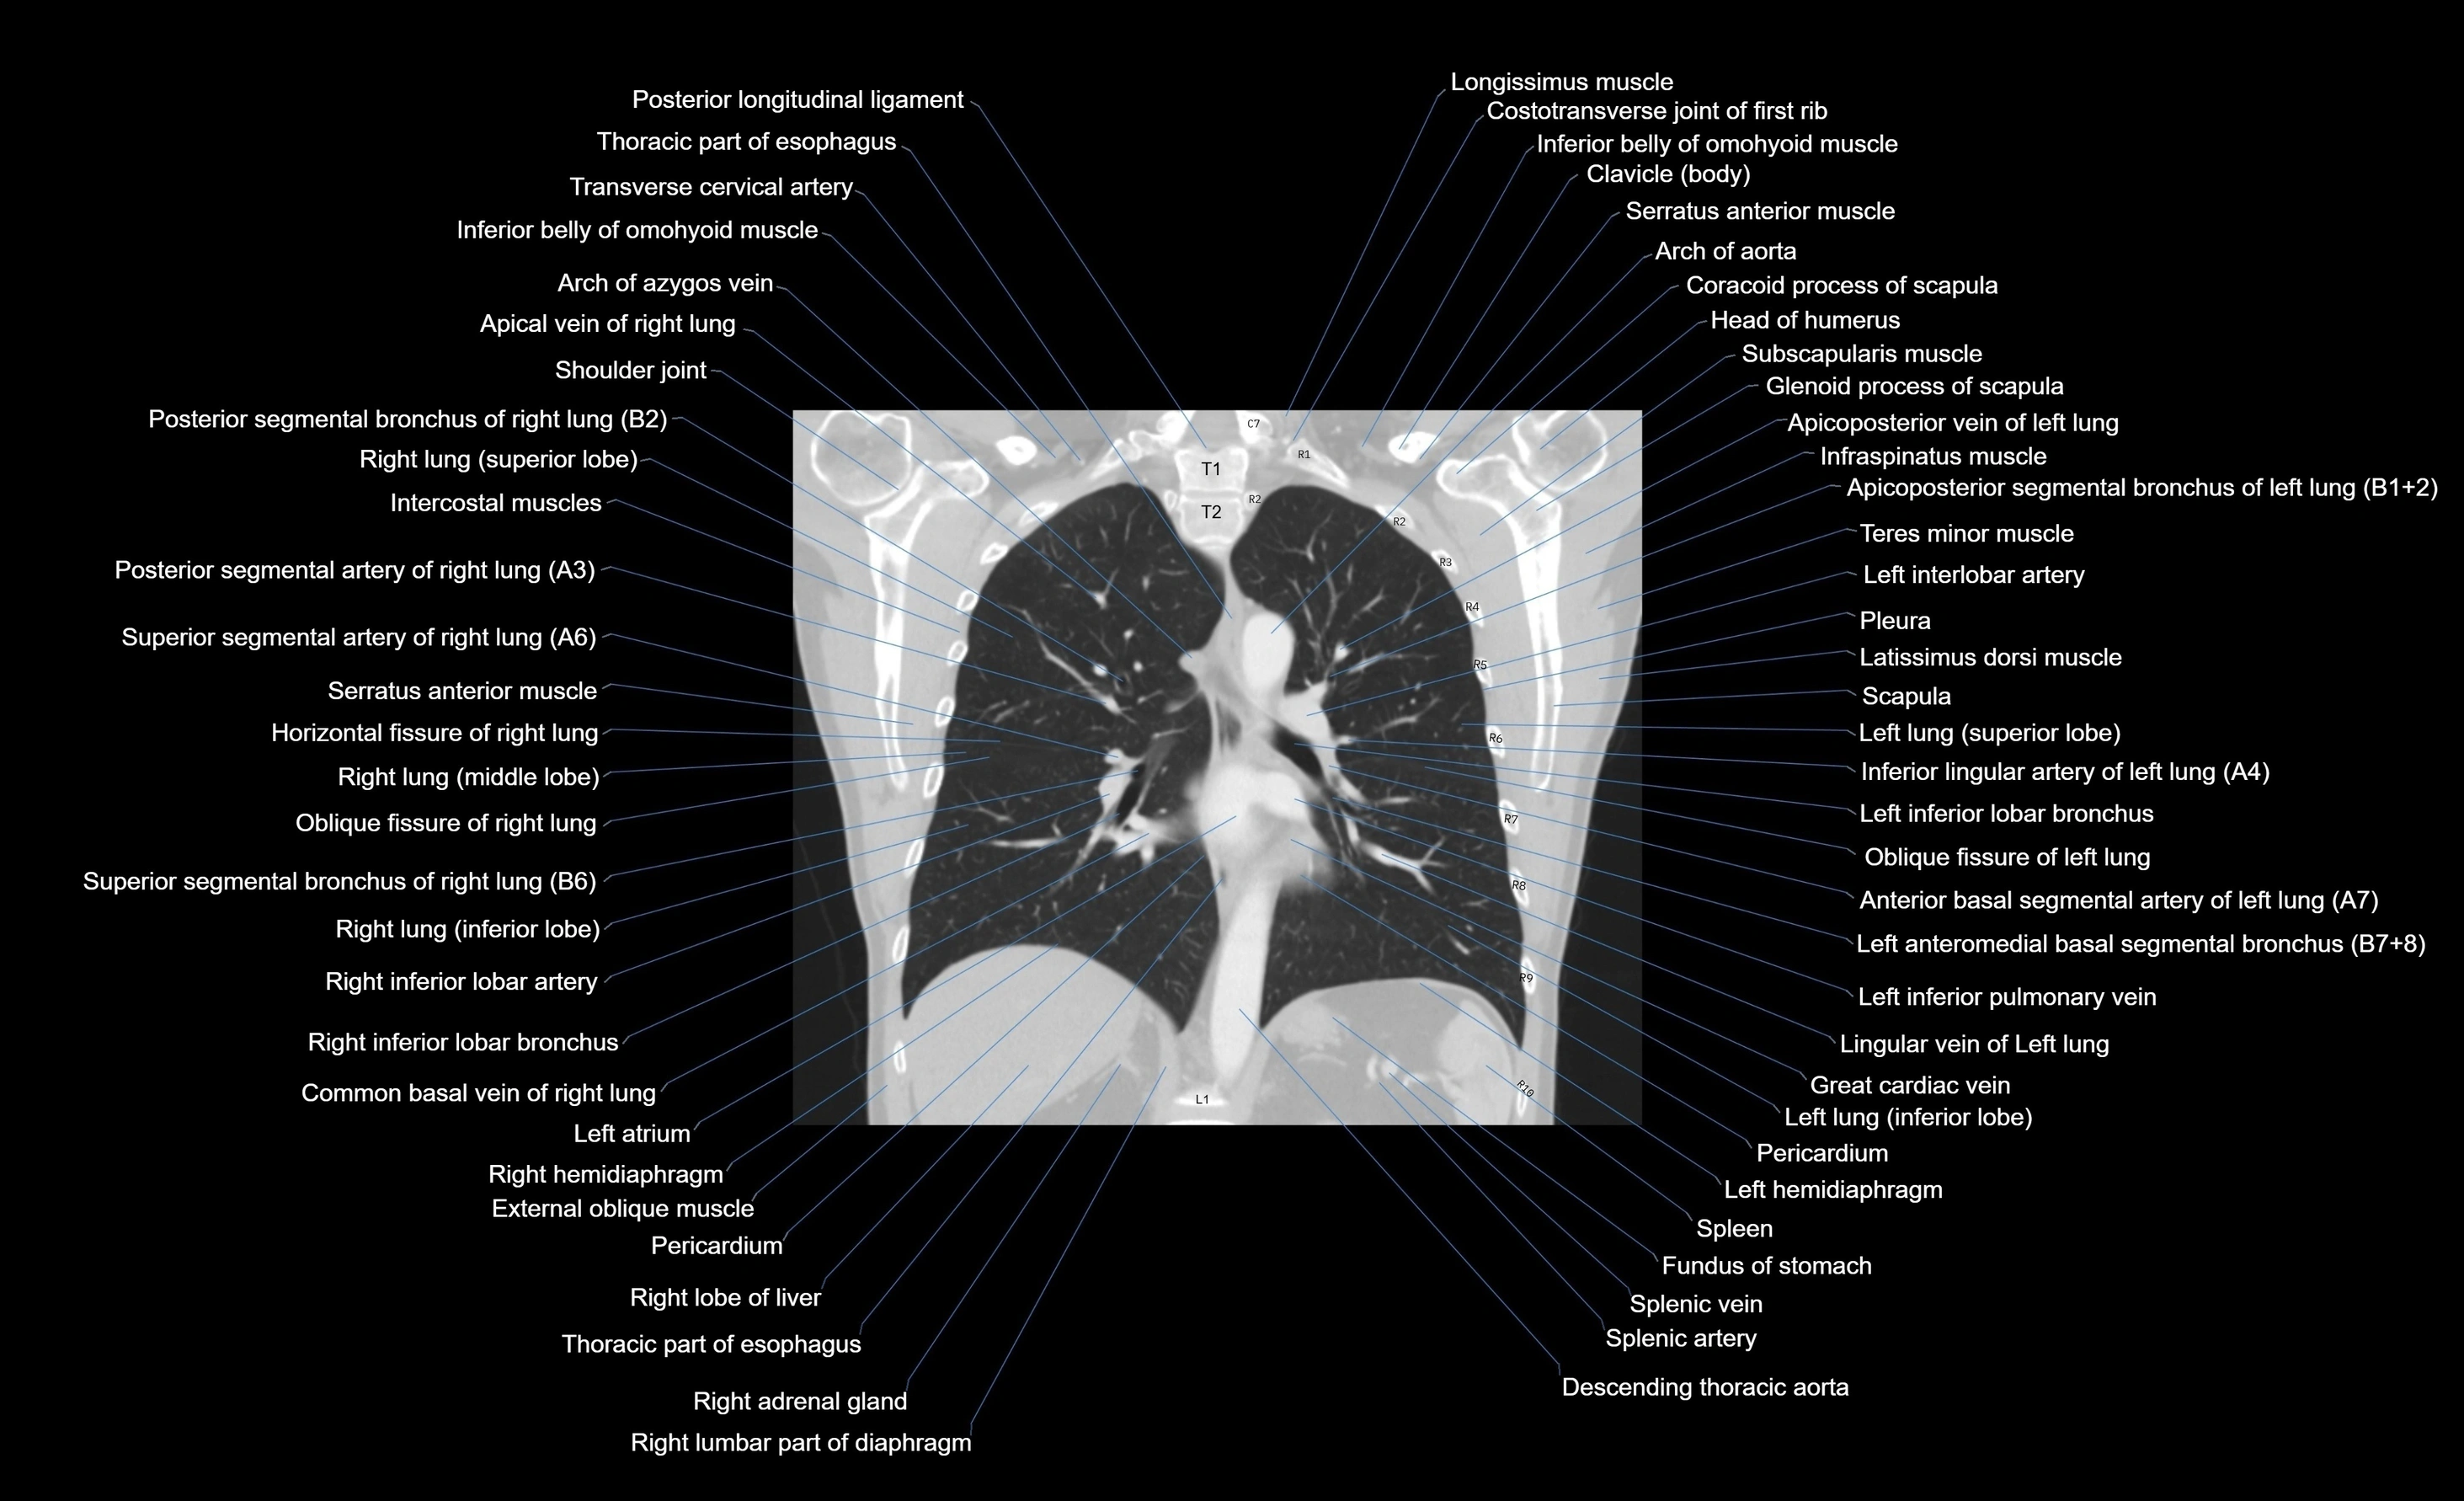

- Anterior basal segmental artery of left lung

- Anteromedial basal bronchus of left lung (B7+8)

- Apicoposterior segmental bronchus of left lung

- Arch of aorta

- Descending thoracic aorta

- Inferior lingular bronchus of left lung (B5)

- Inferior lingular vein of left lung

- Inferior lobe of left lung

- Inferior lobe of right lung

- Lateral basal segmental artery of left lung

- Lateral basal segmental bronchus of left lung (B9)

- Left inferior lobar bronchus

- Left inferior pulmonary vein

- Left interlobar artery

- Left lung (inferior lobe)

- Oblique fissure of left lung

- Oblique fissure of right lung

- Posterior segmental bronchus of right lung

- Right inferior lobar bronchus

- Spleen

- Splenic artery

- Splenic vein

- Superior lobar artery left lung

- Superior segmental artery of left lung

- Superior segmental artery of right lung

- Superior segmental bronchus of right lung (B6)

- Thoracic part of esophagus